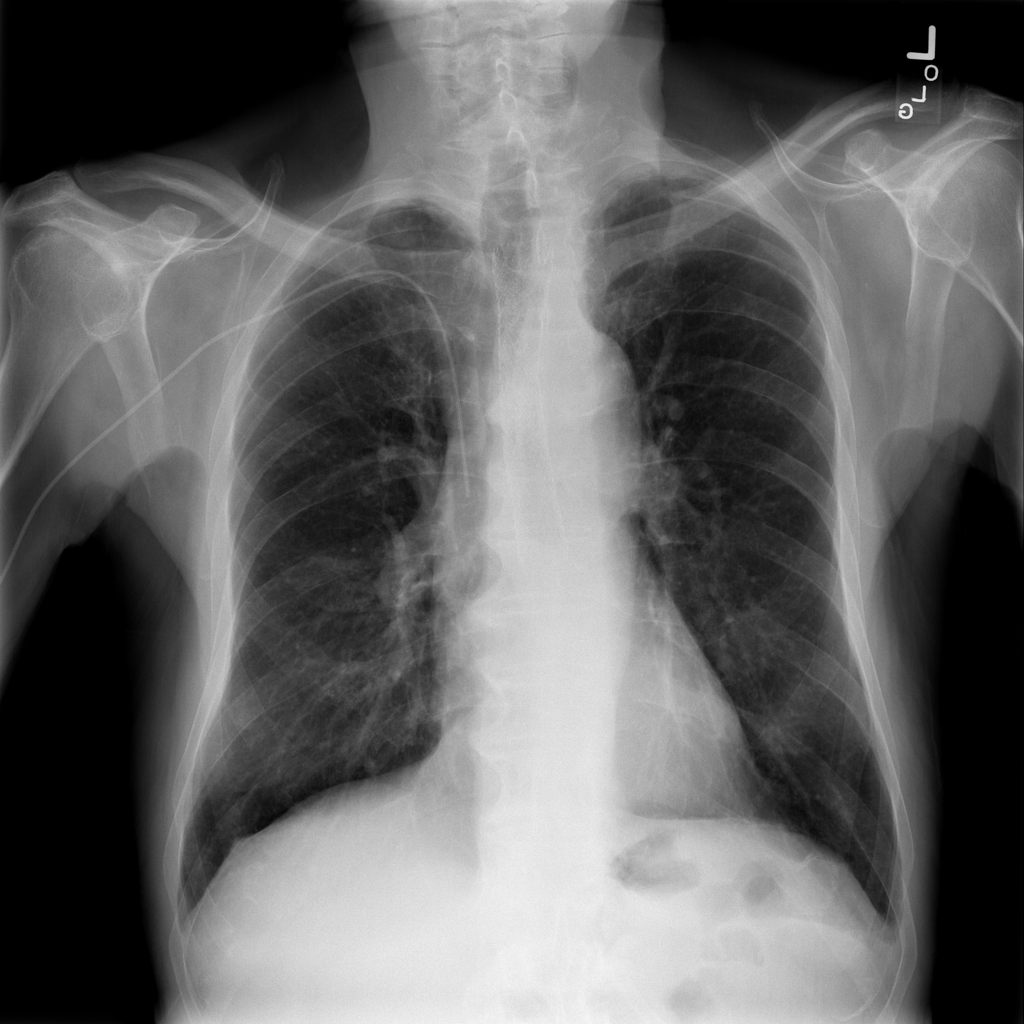

PAT-B0DB · IMG-003Emphysema

PAT-B0DB · IMG-003

PA